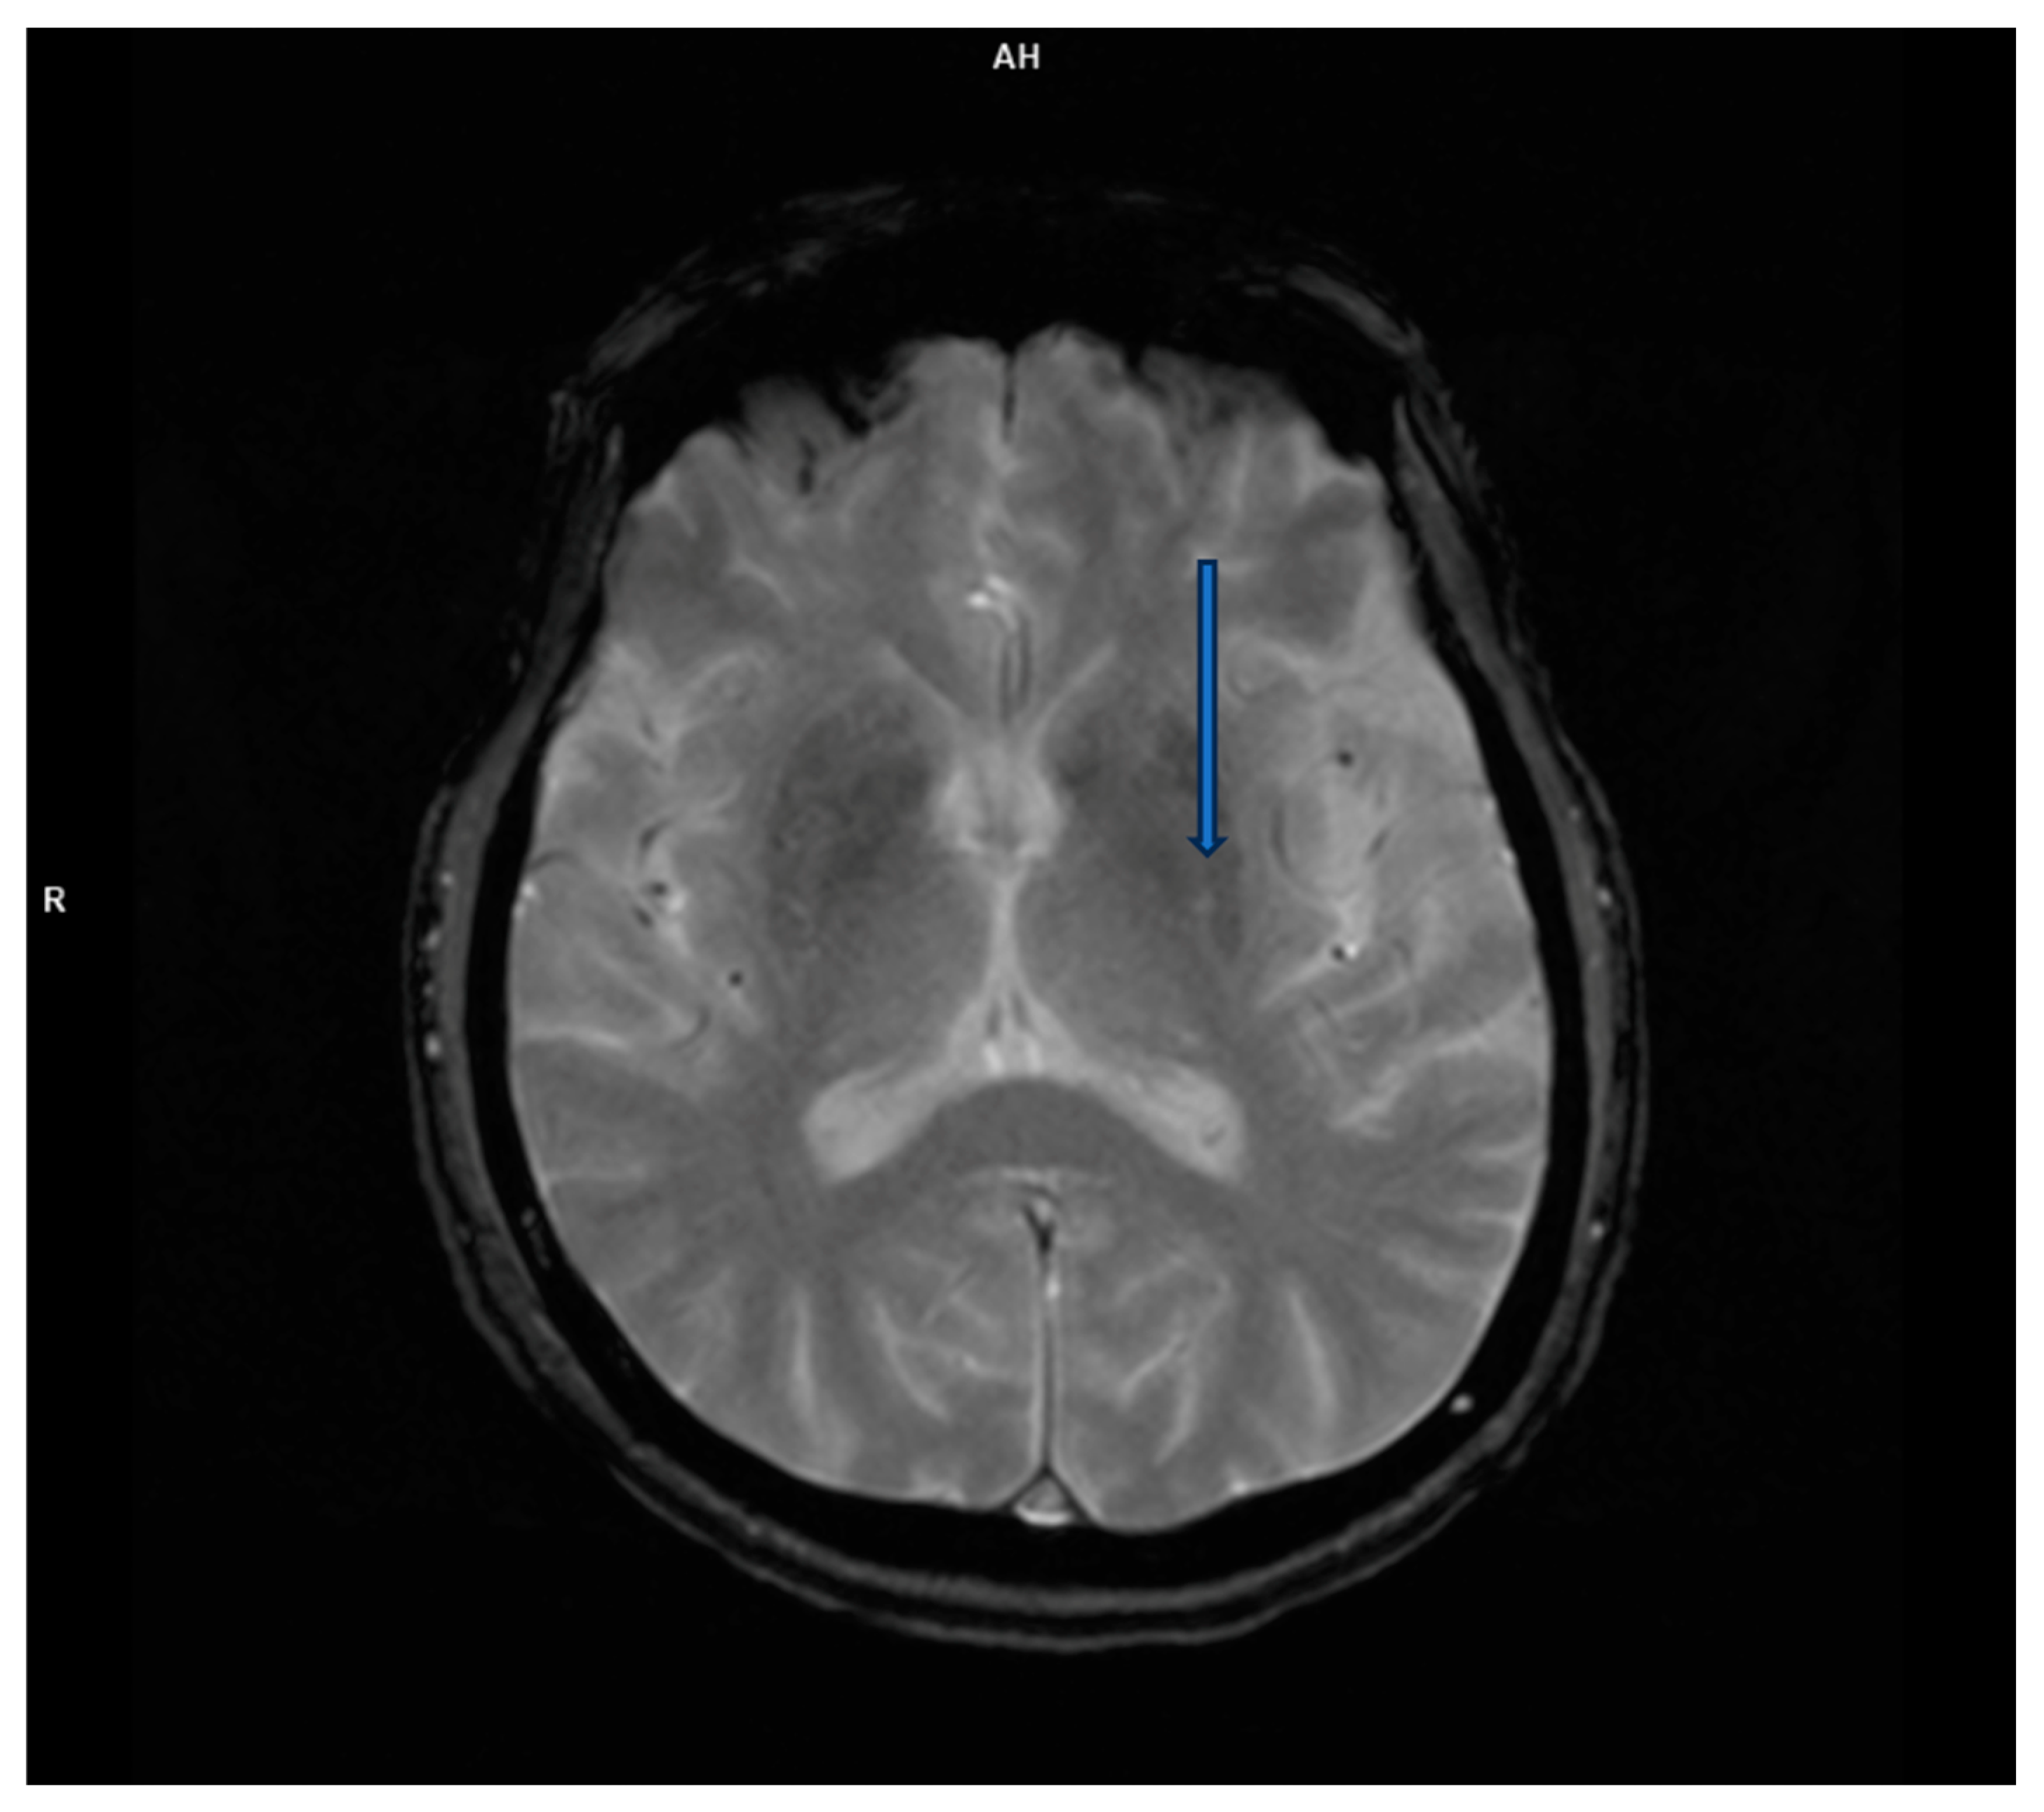

Magnetic resonance imaging (MRI) is a highly sensitive test (over 90%) for detecting herpes simplex encephalitis. Lesions appear hypodense on T1 and hyperintense on T2 and FLAIR, often affecting the temporal lobes, having progressed along the limbic system to the inferior frontal lobes and insular cortex. High-resolution FLAIR can reveal thalamic changes not visible on DWI, while the basal ganglia are usually unaffected. Immunocompromised patients may show atypical patterns outside the frontotemporal regions and often have widespread brain involvement, including the brainstem and cerebellum, but in one-third of patients, there are no pathological changes on MRI [8].

However, brain magnetic resonance imaging (MRI) revealed diffuse cortical atrophy with widened cerebrospinal fluid spaces and prominent perivascular spaces bilaterally in the subinsular region (Figure 1, Figure 2 and Figure 3).

Figure 2. FLAIR transverse MRI scan demonstrates prominent perivascular spaces.